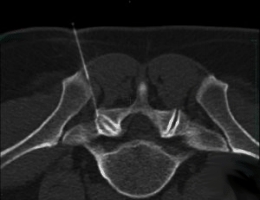

Facettenblockade |

Facettenblockade (Einspritzung in Wirbelgelenke) erfolgt unter

Bildwandlerkontrolle und bei Bedarf mit Hilfe einer

Kontrastmittelinjektion. Die zielgenaue Platzierung der Injektionsnadel innerhalb des betroffenen Wirbelgelenkes, mit Injektion spezieller Medikamente, bewirkt Linderung und mitunter die Vermeidung aufwendiger Operationen. |